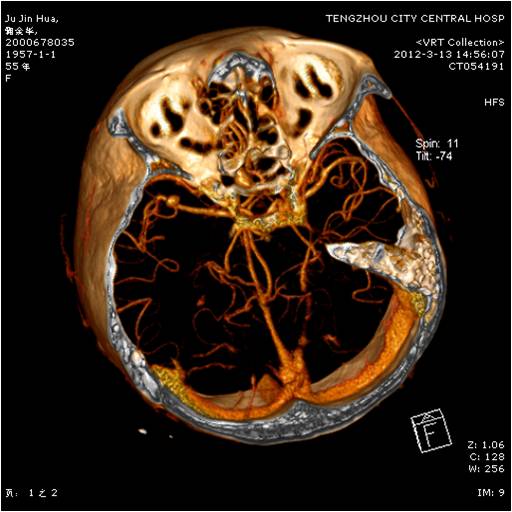

動(dòng)脈瘤夾閉術(shù)前 動(dòng)脈瘤夾閉術(shù)后

應(yīng)用3D-SLICER、神經(jīng)外科導(dǎo)航機(jī)器人、多模態(tài)等綜合方式開展神經(jīng)系統(tǒng)血管疾病的顯微外科及微創(chuàng)介入治療。涵蓋顱內(nèi)動(dòng)脈瘤、腦動(dòng)靜脈畸形、煙霧?。∕oyamoya病)、高血壓腦出血、腦梗塞、頸動(dòng)脈狹窄等出血性、缺血性神經(jīng)血管疾病。率先在魯西南地區(qū)開展并推廣神經(jīng)內(nèi)鏡治療高血壓腦出血,榮獲全國首批腦出血外科診療基地。在復(fù)雜動(dòng)脈瘤開顱夾閉、頸動(dòng)脈內(nèi)膜剝脫、顳淺動(dòng)脈-大腦中動(dòng)脈吻合等方面技術(shù)成熟。